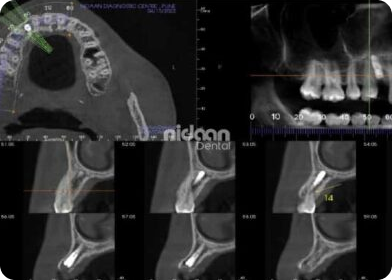

Virtual implant planning & Guide Designing